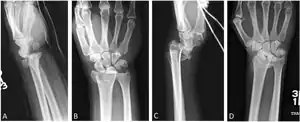

Barton's and reverse Barton's